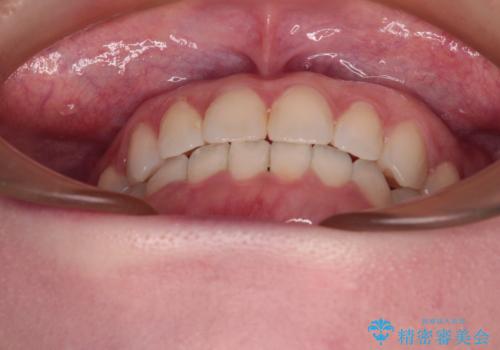

前歯のデコボコをすっきりと インビザライン矯正

- 前歯のデコボコを治したいとのことで来院された患者様です。

下顎が前方位にある方であったため、下顎の歯列全体の後方移動とIPR(歯と歯の間を削る)によってデコボコが解消するように設計し、インビザラインにより治療を行うこととしました。